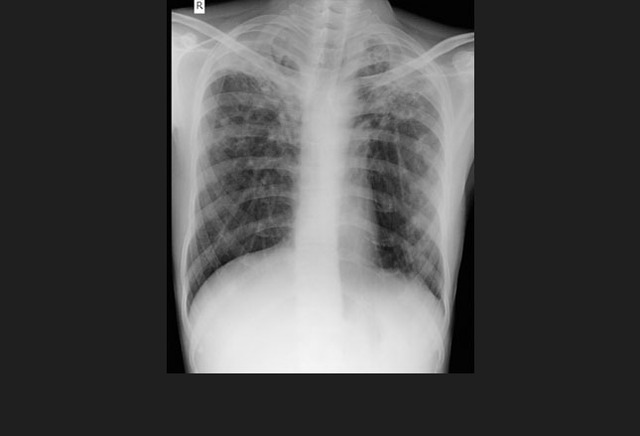

图10. 一位继发于慢性结核的患者双侧肺尖胸膜实质疤痕

答案:D、体重继续减轻。

随着有效的抗痨治疗,患者体重应当增加。当出现持续发热、胸部X线恶化、咳嗽增加、持续夜间盗汗及痰培养迟迟不能转阴时均应考虑到多耐药结核感染的可能。